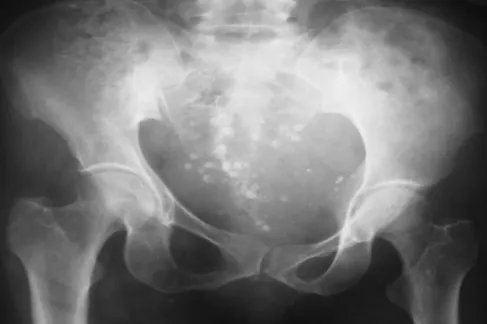

概述女性的骨盆是躯干和下肢之间的骨性连接,是支持躯干和保护盆腔脏器的重要结构。女性骨盆又是胎儿娩出时必经的骨性产道,其大小、形态与分娩密切相关。通常女性骨盆较男性骨盆宽而浅,有利于胎儿娩出。骨盆形态及组成骨间各径线异常可导致异常分娩。位置女性骨盆在躯干下部,骨盆下部与两侧下肢相连。不同的人骨盆位置略有不同,但整体位置是一样的。女性骨盆可分为大骨盆和小骨盆。大骨盆,又称假性骨盆,属于腹部。小骨盆,位于下背部,与女性生殖等一系列生理活动有重要关系,被称为真骨盆。女性骨盆包含许多骨盆器官,如女性子宫附件和一部分肠道。类型1、女型骨盆入口呈椭圆形,入口横径略长于前后径,骨盆侧壁平直。这是最常见的骨盆类型,属于女性的正常骨盆。

扁平型骨盆图片特征女性骨盆的特征是形状短而宽,上口呈宽圆形或椭圆形,下口的矢状径和横径比男性宽,尾骨的活动性更大,坐骨结节外翻,耻骨联合相对较宽。